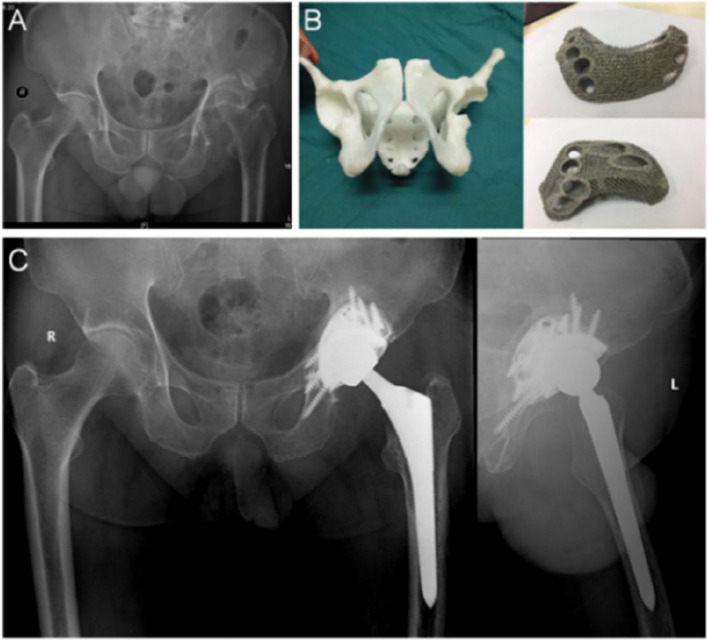

Methods: We reviewed three cases of Paprosky type III acetabular defects reconstructed using personalized 3D-printed porous titanium alloy augments. Finite element analysis (FEA) simulated the defects, utilizing a commercial augment as a control. Stress distribution within the augments, fixation screws, acetabular cups, and surrounding bone was analyzed under simulated single-leg standing (1 × body weight), walking (4 × BW), and jogging (6 × BW) loading conditions, with comparisons made to the control.

Results: Under all loading conditions, the peak stresses observed on the augment screws and acetabular cups in all three cases were lower than the buckling strength of titanium alloy and were consistently lower than those recorded in the control group. This indicates that the personalized augments provided stable support for acetabular cup fixation, aiding in the restoration of the hip rotation center and lower limb length.